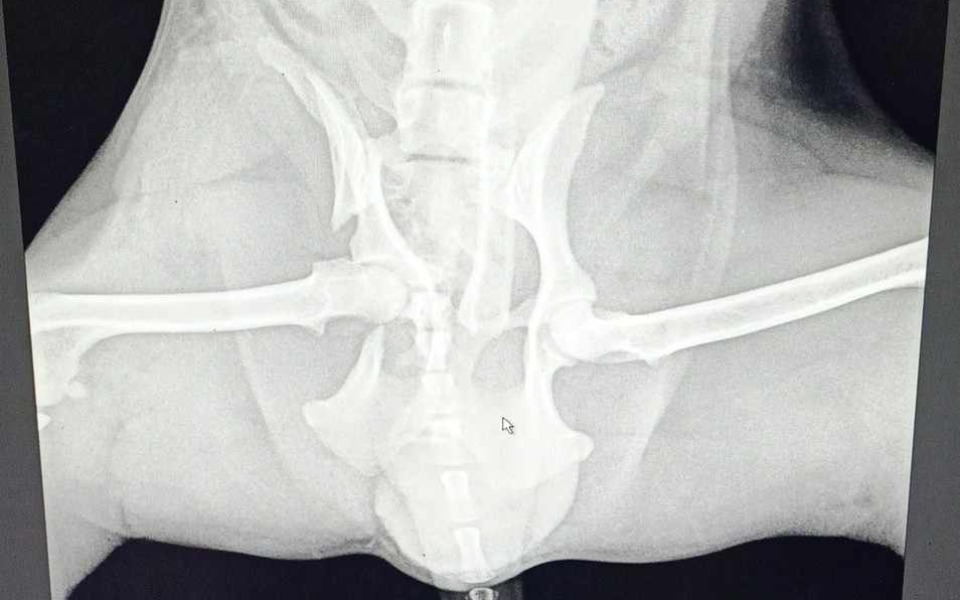

Witam wszystkich. Jimmy jest dwu letnim yorkiem, który uległ wypadkowi komunikacyjnemu, w skutek czego doznał złamania miednicy. Piesek siusia krwią i nie trzyma moczu dlatego potrzebna jest kosztowna operacja aby ulżyć mu w cierpieniu i pomóc wrócić do zdrowia.